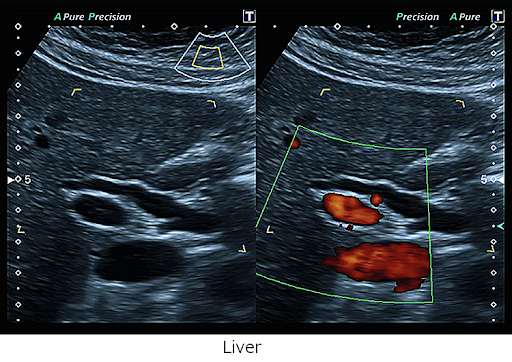

Только самое лучшее качество изображения позволяет быстро и с уверенностью поставить диагноз. Каждая из уникальных технологий визуализации Xario обеспечивает лучшую четкость и разрешение за счет снижения шума, усиления сигнала и улучшения визуализации.

Canon Medical Systems' High Density Architecture формирует основу для превосходного качества изображения и позволяет вам видеть больше деталей и делать больше исследований. Благодаря всесторонним возможностям улучшения изображения и настройке глубины до 40 см, Canon Medical Systems, несомненно, является лидером в предоставлении лучших в своем классе изображений для диагностики различных заболеваний.

Технология Precision Imaging улучшает определение границ и делает края структур более четкими.

D-THI - Differential Tissue Harmonic Imaging - Дифференциальная тканевая гармоника

Увеличивает контрастность и пространственное разрешение на больших глубинах и у пациентов с плохой визуализацией.

Технология ApliPure+ позволяет достигать беспрецедентной однородности и детализации при сохранении клинически значимых маркеров.

ADF - Advanced Dynamic Flow™* позволяет визуализировать мельчайшие кровеносные сосуды и регистрировать кровоток с непревзойденной точностью и детализацией.